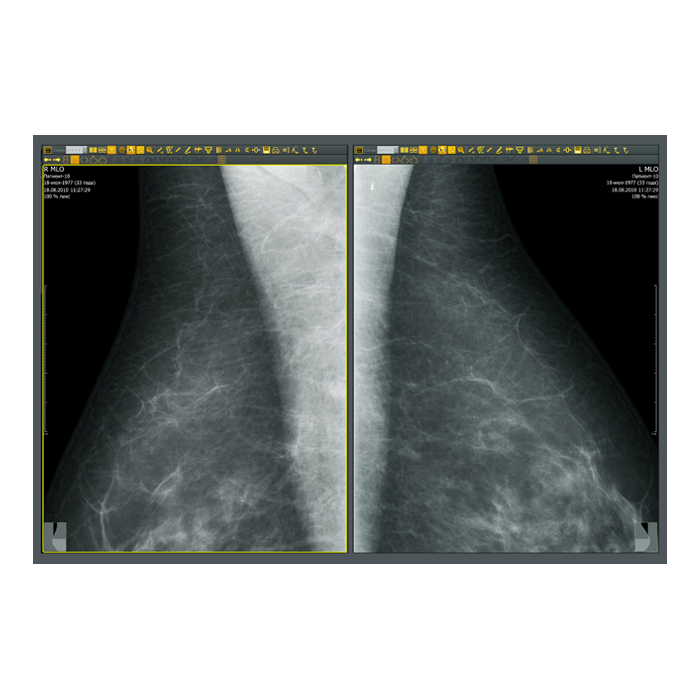

- Рентгенология